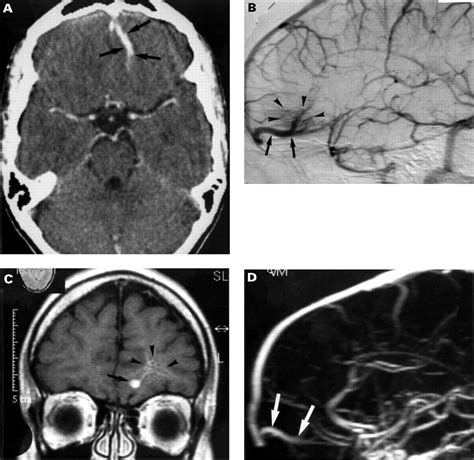

Diagnosing a DVA typically involves imaging studies, such as magnetic resonance imaging (MRI) or computed tomography (CT) scans. These imaging techniques can reveal the characteristic appearance of DVAs, which include:

• Abnormal venous channels

• Dilated venous structures

• Caput medusae appearance, where the venous channels radiate outward like the head of Medusa

In some cases, additional imaging studies, such as angiography, may be performed to better visualize the venous drainage patterns and rule out other vascular malformations.